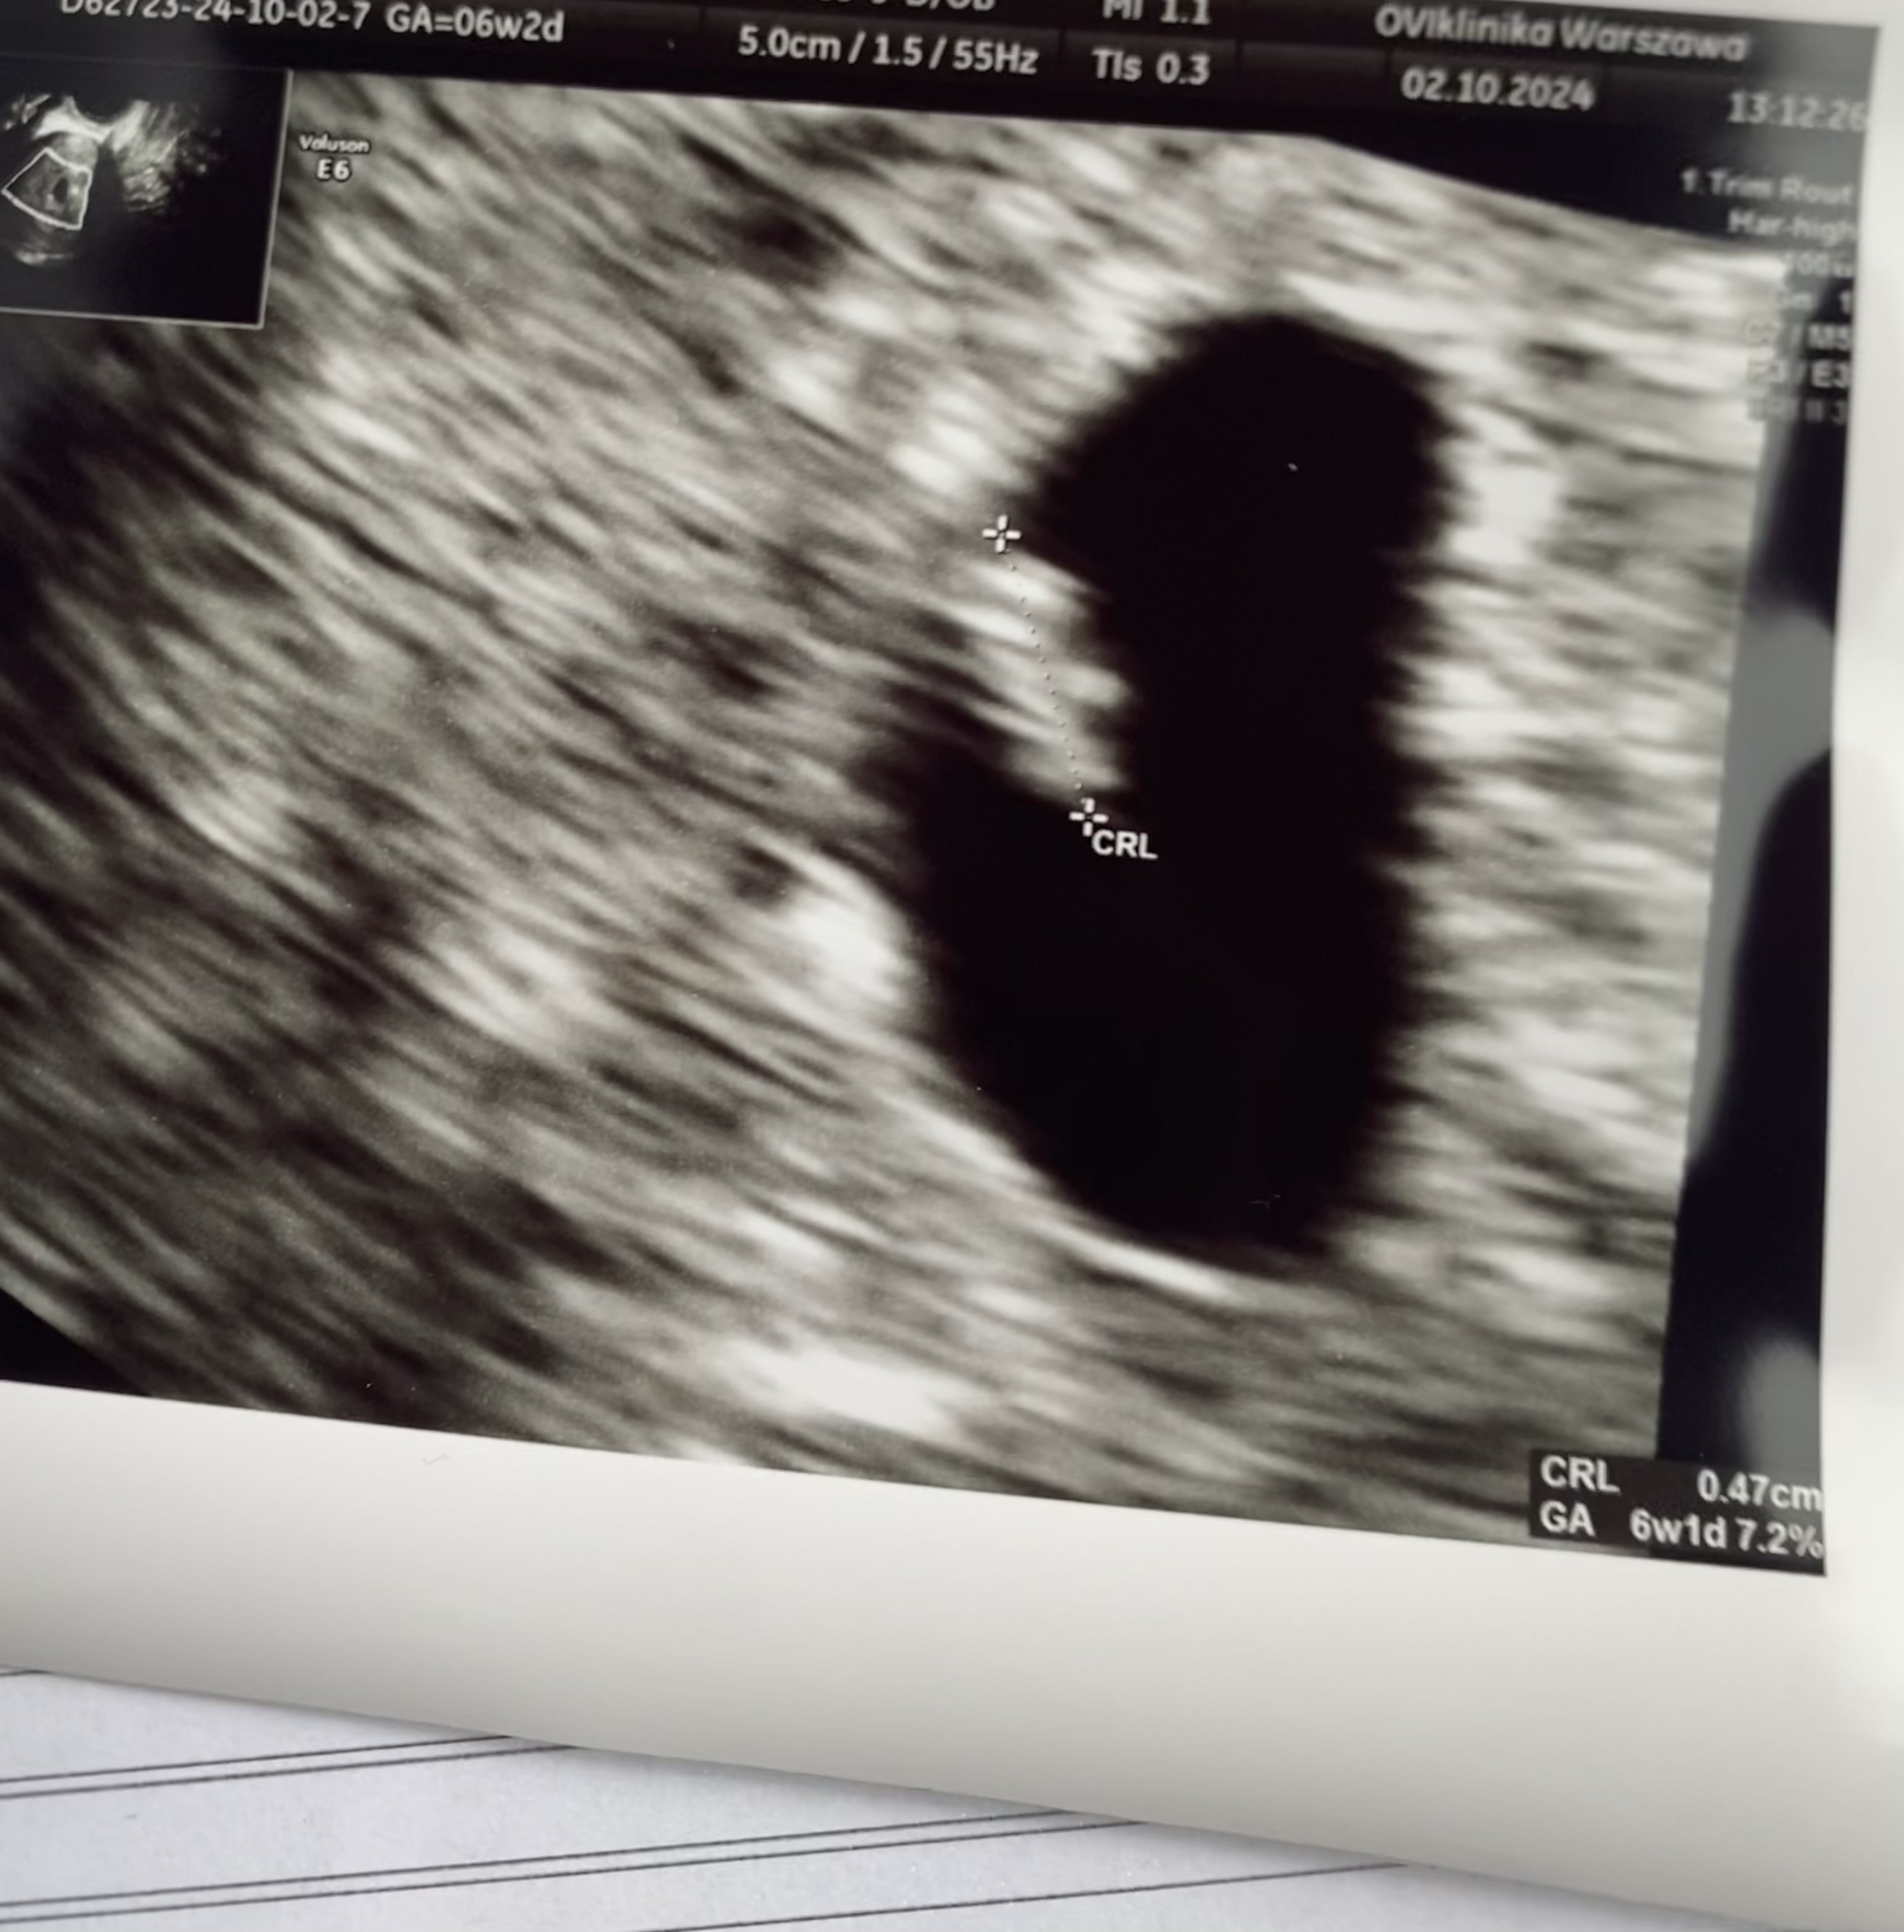

Mały wielki człowieczek

Cudowny widok! Gratulacje! Juz niedługo będziesz gruba (w pozytywnym znaczeniu tego słowa)Mały wielki człowieczekserduszko bije wszystko ok teraz wizyta za 2 tyg na zejście z leków pół drogi płakałam z szczęścia jest mój mały wielki cud